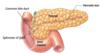

Label the GI tract

Label the sphincters

Label the stomach

Label the small intestine